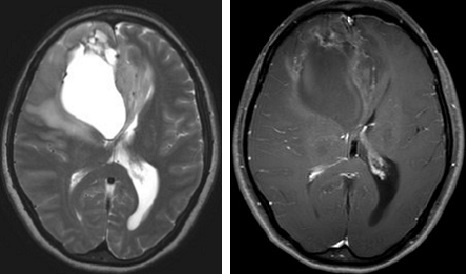

脳を構成する細胞の中で、神経膠細胞(グリア細胞)と呼ばれる細胞からできる腫瘍の総称です。神経膠細胞の中にも様々な種類があり、種類によって形や成長も異なるため、病理学的分類も非常に複雑です。脳に発生する腫瘍の中でも頻度が高く全脳腫瘍中の約1/3を占めます。原発性脳腫瘍は腫瘍の形態学、細胞学、分子遺伝学、免疫組織学的特徴を併せて評価するWHO分類と呼ばれる分類法が広く普及し、治療手段の選択と成績を表す指標となっています。神経膠腫の場合、予後の良好な方から不良の方へグレード1〜4に分類され、神経膠腫グレード2は低悪制度、3と4を悪性神経膠腫と総称しています。グレード1は小児発生が多いのに比べ成人ではグレード2,3,4の発生が主であり、いずれも脳内に浸潤性に発育するとされています。

頭痛・片麻痺・失語・意識障害・痙攣発作など腫瘍が発生する部位に応じた症状が見られます。グレード1,2は症状がゆっくり進行しますが、グレード3,4の悪性度の高い腫瘍では症状が急速に進行します。神経膠腫の10%程度に脳内出血を伴うため、脳卒中との鑑別が難しい場合があります。脳ドックなどで偶然見つかることもあります。脳は前頭葉・側頭葉・頭頂葉・後頭葉・脳幹・小脳など、部位によって様々な機能を持っていますので、脳腫瘍が頭蓋内のどこに発生するかによって様々な症状をおこします。

グレード4:神経膠腫の中でも進行が早く最も悪性度が高い腫瘍で膠芽腫(グリオブラストーマ)と呼ばれます。5年生存率は約15%未満と非常に悪性度の高い腫瘍です。